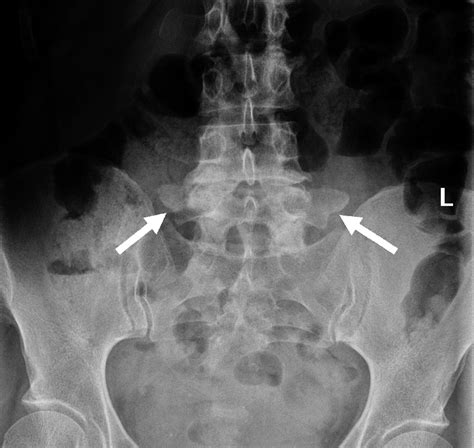

Diagnosing partial sacralization of L5 typically involves a combination of physical examination and imaging tests. Common diagnostic methods include:

• X-rays: To visualize the spine and identify any bony abnormalities.

• partial sacralization of l5 radiology